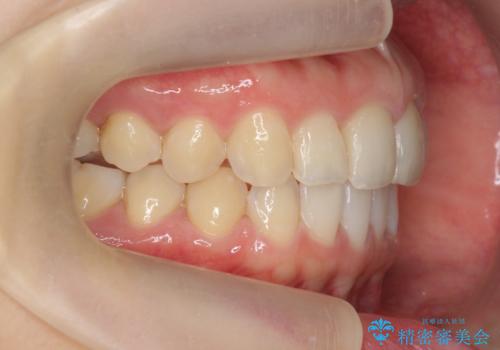

出っ歯に見える前歯の改善 部分ワイヤーとマウスピース矯正

- 出っ歯に見える前歯の改善を希望され、来院されました。

マウスピースでは改善の難しい歯の動きを部分ワイヤー矯正で整えたのち、奥歯の噛み合わせや細かい歯の並びをマウスピース矯正インビザラインで整えていきます。

最終的な前歯の並びに大変満足いただくことができました。